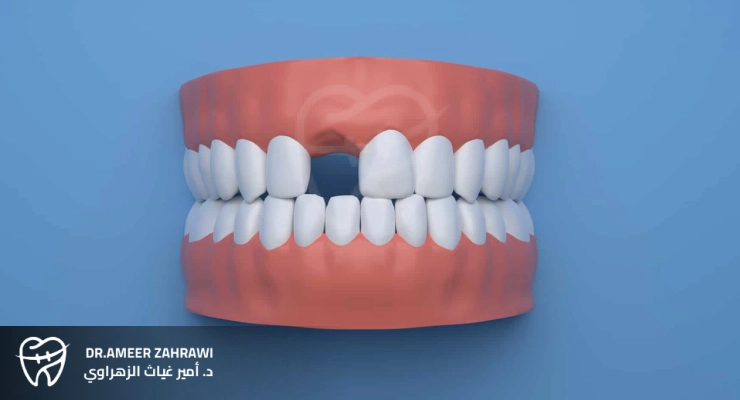

Replacing missing teeth is a crucial part of dental care. It not only restores a person’s smile, but also supports overall oral health and proper function. From traditional options like dentures and dental bridges to modern solutions such as dental implants, there are many ways to restore lost teeth.This article takes an in-depth look at the different options available for replacing missing teeth, highlighting the benefits and considerations of each approach to help people make informed decisions about their oral health.

Replacing missing teeth refers to restoring one or more lost teeth using various dental treatments and procedures. When a tooth is lost due to decay, gum disease, trauma, or congenital issues, it can significantly affect a person’s oral health, appearance, and self-confidence.Dentists offer a range of solutions to replace missing teeth with the goal of closing the gaps in your smile, maintaining proper dental function, and preventing potential complications that can arise from tooth loss.

There are several important reasons that make replacing missing teeth necessary, including functional, aesthetic, and health-related factors. Leaving gaps untreated can lead to shifting of adjacent teeth, bite problems, difficulty chewing, speech changes, bone loss in the jaw, and increased risk of further dental issues.